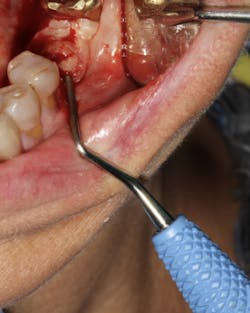

An implant that has lost integration can suffer from fibrous downgrowth (encapsulation) of the entire implant body (figure 1). This tissue acts a barrier to bone-to-implant contact and osseointegration of the replacement implant.6 It is imperative to thoroughly debride the implant socket and meticulously remove all soft tissue prior to implant placement. Proper instrumentation will allow the clinician to reach the apex of the implant socket and be sharp enough to perform curettage on the osseous walls of the socket (figure 2). After complete tissue removal, chemical modification is the next step.

Figure 2: Slade Blade socket curette (Paradise Dental Technologies) being used to remove fibrous soft tissue from the residual implant socket